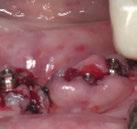

Ejecución técnica quirúrgica mediante férula guiada Bajo anestesia infiltrativa realizamos extracciones atraumáticas de todas las piezas a excepción de los dientes que actúan como anclaje o pilares para la fijación de la férula quirúrgica (Figuras 20 y 21). Seguidamente insertamos la férula comprobando una buena adaptabilidad y estabilidad

Figura Figura en posición ideal. Figura Figura

Figura

de dientes estratégicos para fijar la férula quirúrgica.

Figura 23. Férula quirúrgica inferior. Figura 24. Fresado guiado con férula y cucharilla. Figura 20. Extracciones dentales. 21. Conservación Figura 22. Férula quirúrgica superior. Figura 25. Inserción de implante RSX de Bego a través de férula quirúrgica. Figura 27. Conexión de pilar angulado multiplus sobre implante. Figura 26. Implante insertado en lecho a través de férula quirúrgica. Figura 28. Muestra del perfecto paralelismo tras la colocación de pilares angulados multiplus. Figura 29. ScanBody sobre pilares transepiteliales.